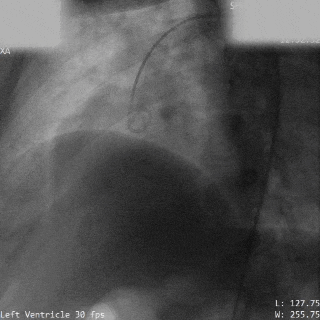

释放前瓣上造影,分流明显减少(左);牵拉试验,确认封堵器稳定(右)